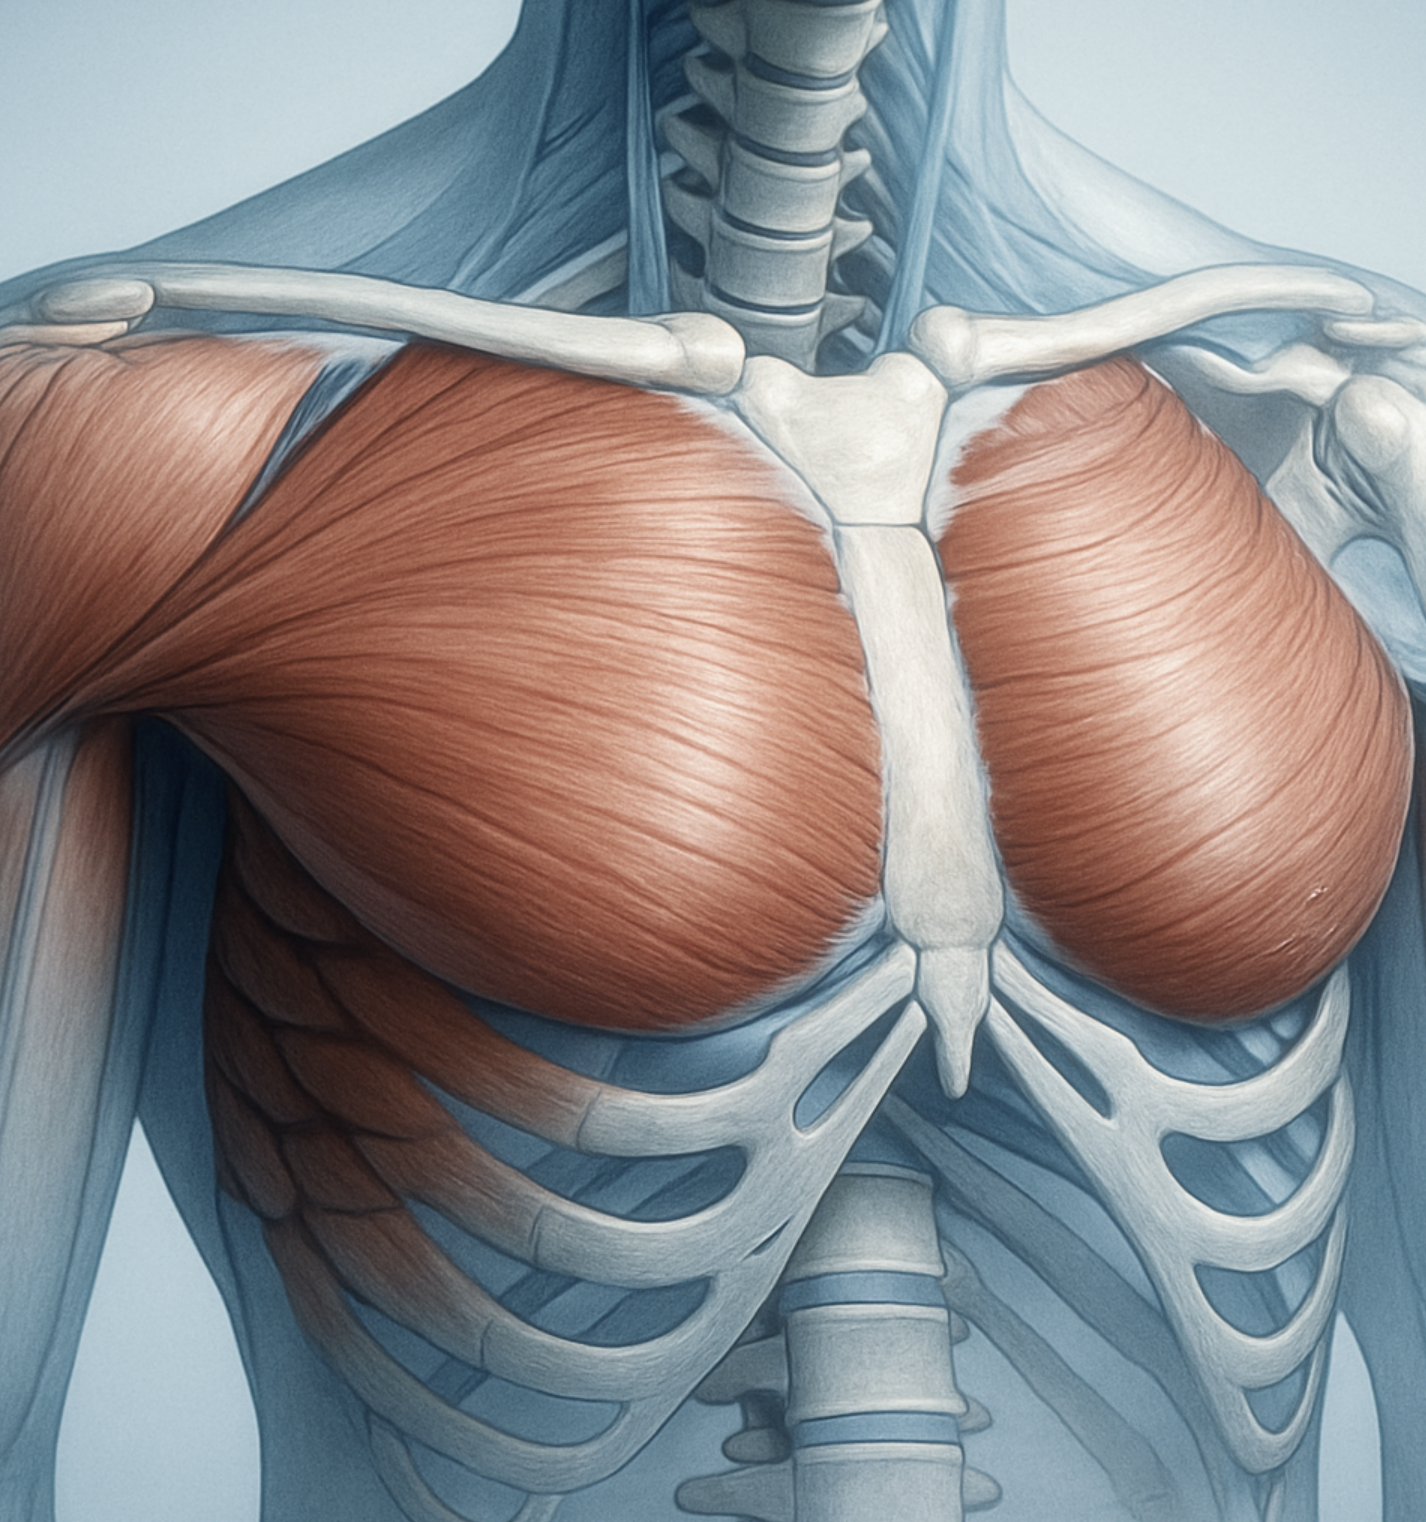

가장 흔한 범인, 근육과 뼈의 문제

오른쪽 가슴 부위의 불편함을 유발하는 가장 흔한 원인은 바로 ‘근골격계’ 문제입니다. 무리한 운동으로 가슴 근육이 놀랐거나, 잘못된 자세로 오랫동안 앉아 있으면서 갈비뼈 사이의 근육이나 연골에 무리가 간 경우입니다. 마치 오랫동안 쓰지 않던 문을 갑자기 열 때 ‘삐걱’ 소리가 나는 것과 비슷합니다.

이러한 근골격계 통증의 가장 큰 특징은, 특정 부위를 손가락으로 눌렀을 때 아픔이 더 심해지는 ‘압통’이 있다는 점입니다. 또한, 몸을 특정 방향으로 비틀거나 팔을 움직일 때, 혹은 깊은 숨을 쉴 때 통증이 더 명확하게 느껴지기도 합니다. 이럴 때는 충분한 휴식과 함께 가벼운 스트레칭을 해주는 것이 가장 좋은 해결책이 될 수 있습니다.